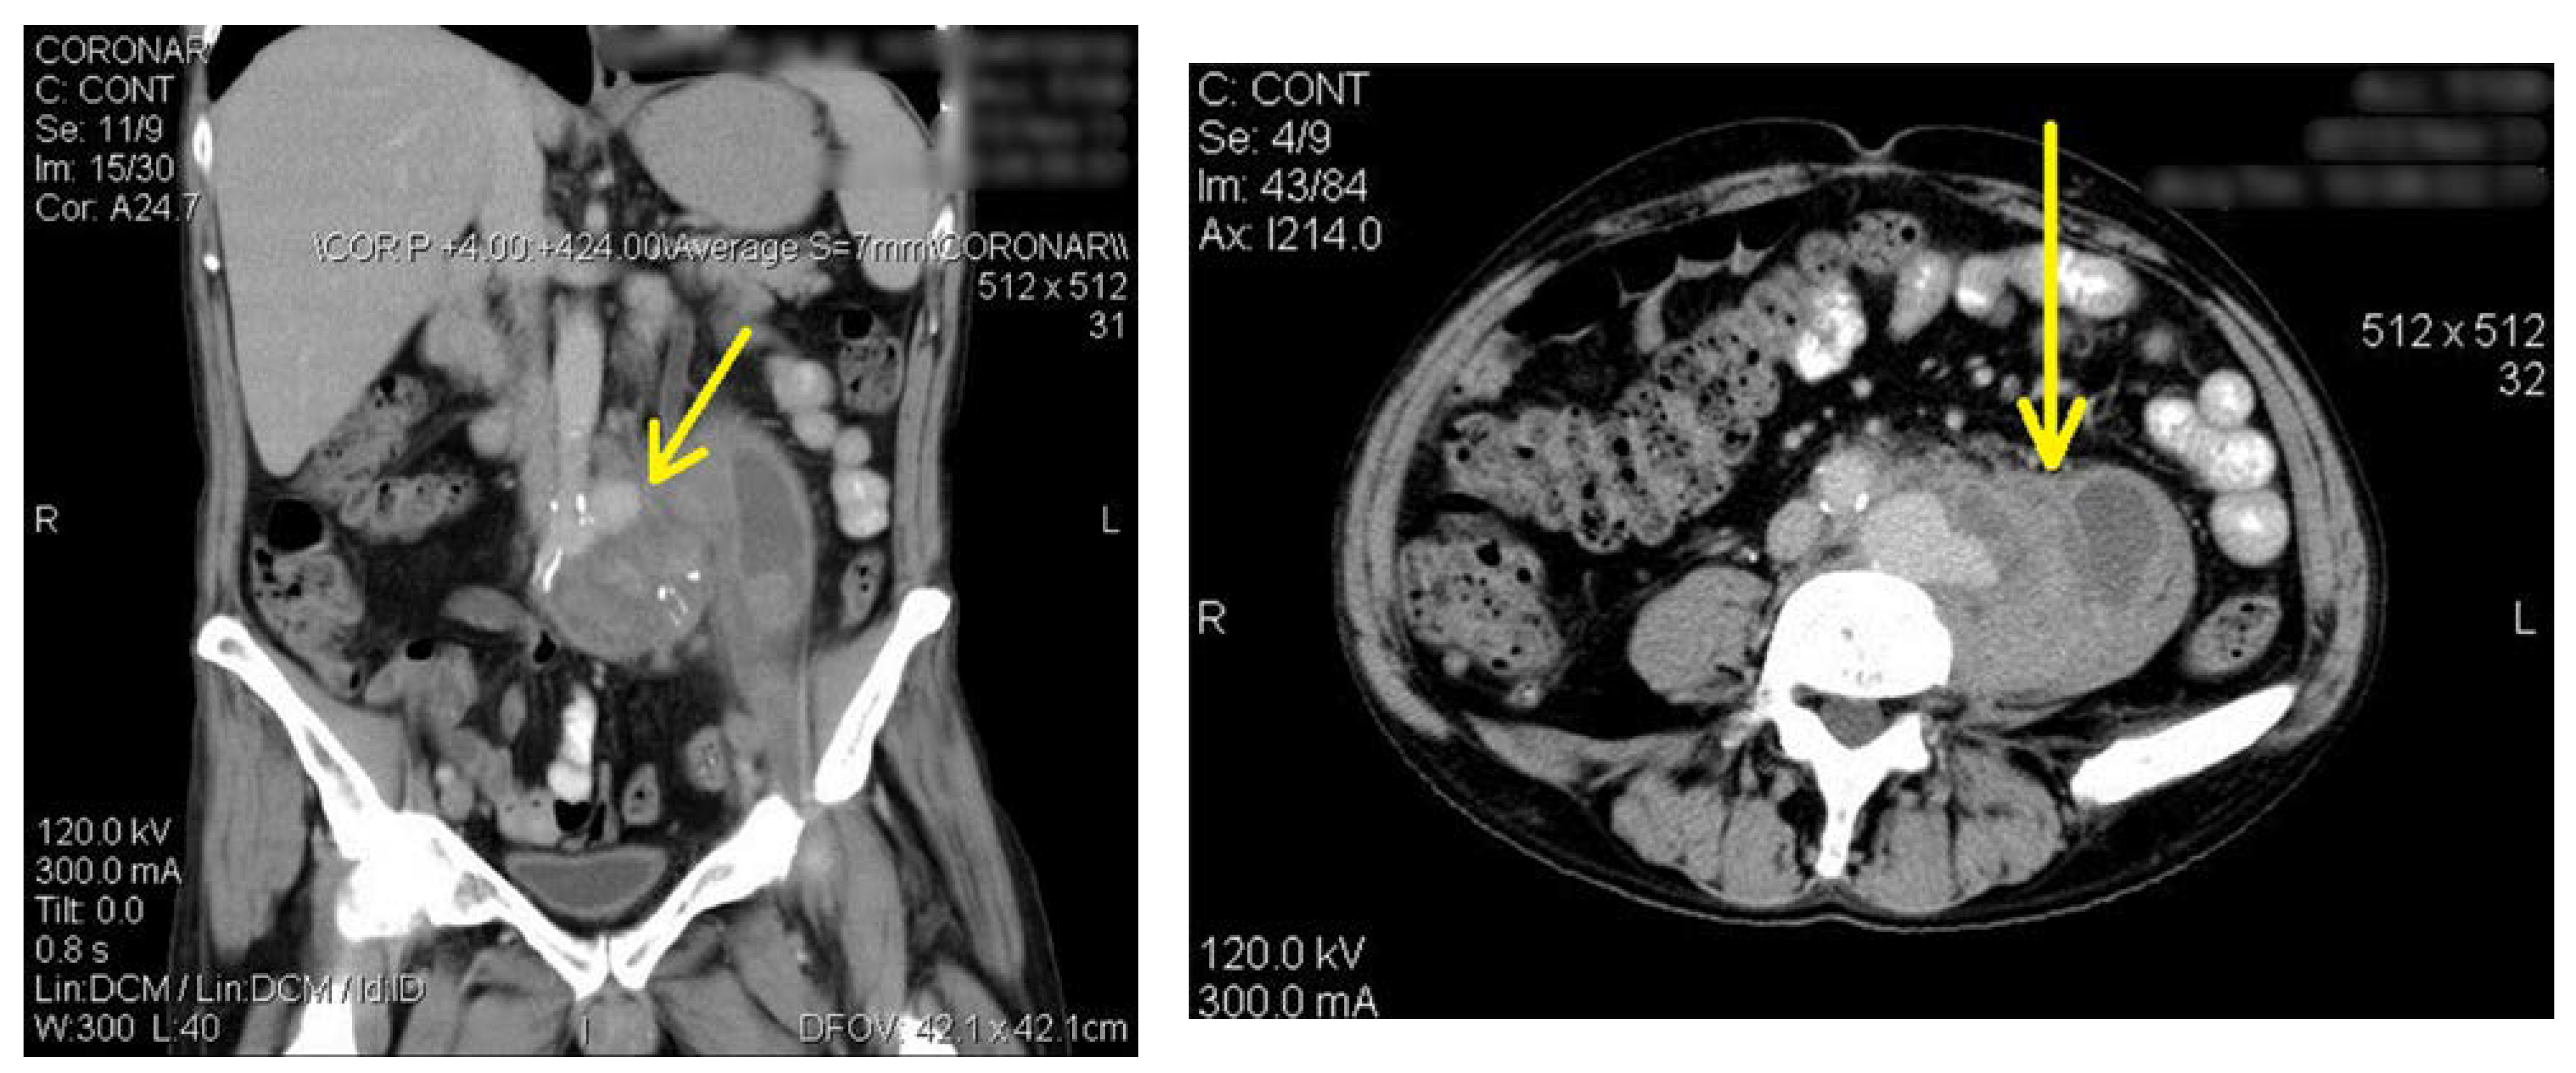

After 3 weeks, he came back in emergency for relapsed fever. The low back pain had increased, accompanied by the occurrence of left hip pain and functional impotence. The clinical exam revealed high fever, of 39.1 °C, blood pressure of 180/90 mmHg, heart rate of 125 bpm, respiratory frequency of 25/min, tenderness on percussion in the left lumbar region, swelling of the left leg, pain and disability of the left hip joint. He received meropenem as first choice antibiotic. Salmonella group C was identified in the blood cultures after 3 days. Based on the antibiogram, therapy was de-escalated to ceftriaxone and ciprofloxacin. The fever dropped within 2 days, but inflammatory signs appeared in the left leg, while the pain in the back and the left hip persisted. After five days the patient complained of a sensitive, soft swelling, which measured 5/7 cm, in the left inguinal region. The computed tomography scan with contrast of the abdomen and pelvis (Figure 2a,b) ruled out the suspicion of arthritis in the left hip and revealed an aneurysm of the left common iliac artery. Under coverage of antibiotic therapy, the aneurysm was excised, the aortic bifurcation removed and an aortic bifemoral bypass was performed. The bacterial culture of the excised aneurysm wall was positive for Salmonella group C. The patient continued ceftriaxone for six weeks and was cured when he was discharged. He gave up alcohol and smoking. He follows ambulatory antiplatelet and antihypertensive treatments and is waiting to be evaluated for hepatitis C treatment.

Figure 2. (a). Abdominal computed tomography with oral and intravenous contrast in coronal section: aneurysm in the external iliac artery; at the level of the aortic bifurcation, overlapping the left iliac artery, a mass with heterogeneous density, fluid before and after contrast, with inside calcification, well delimited; iliac vessel with right wall calcifications. (b). Abdominal computed tomography with oral and intravenous contrast in transversal section: aneurysm in the external iliac artery; at the level of the aortic bifurcation, overlapping the left iliac artery, a mass with heterogeneous density, fluid before and after contrast, with inside calcification, well delimited; iliac vessel with right wall calcifications.